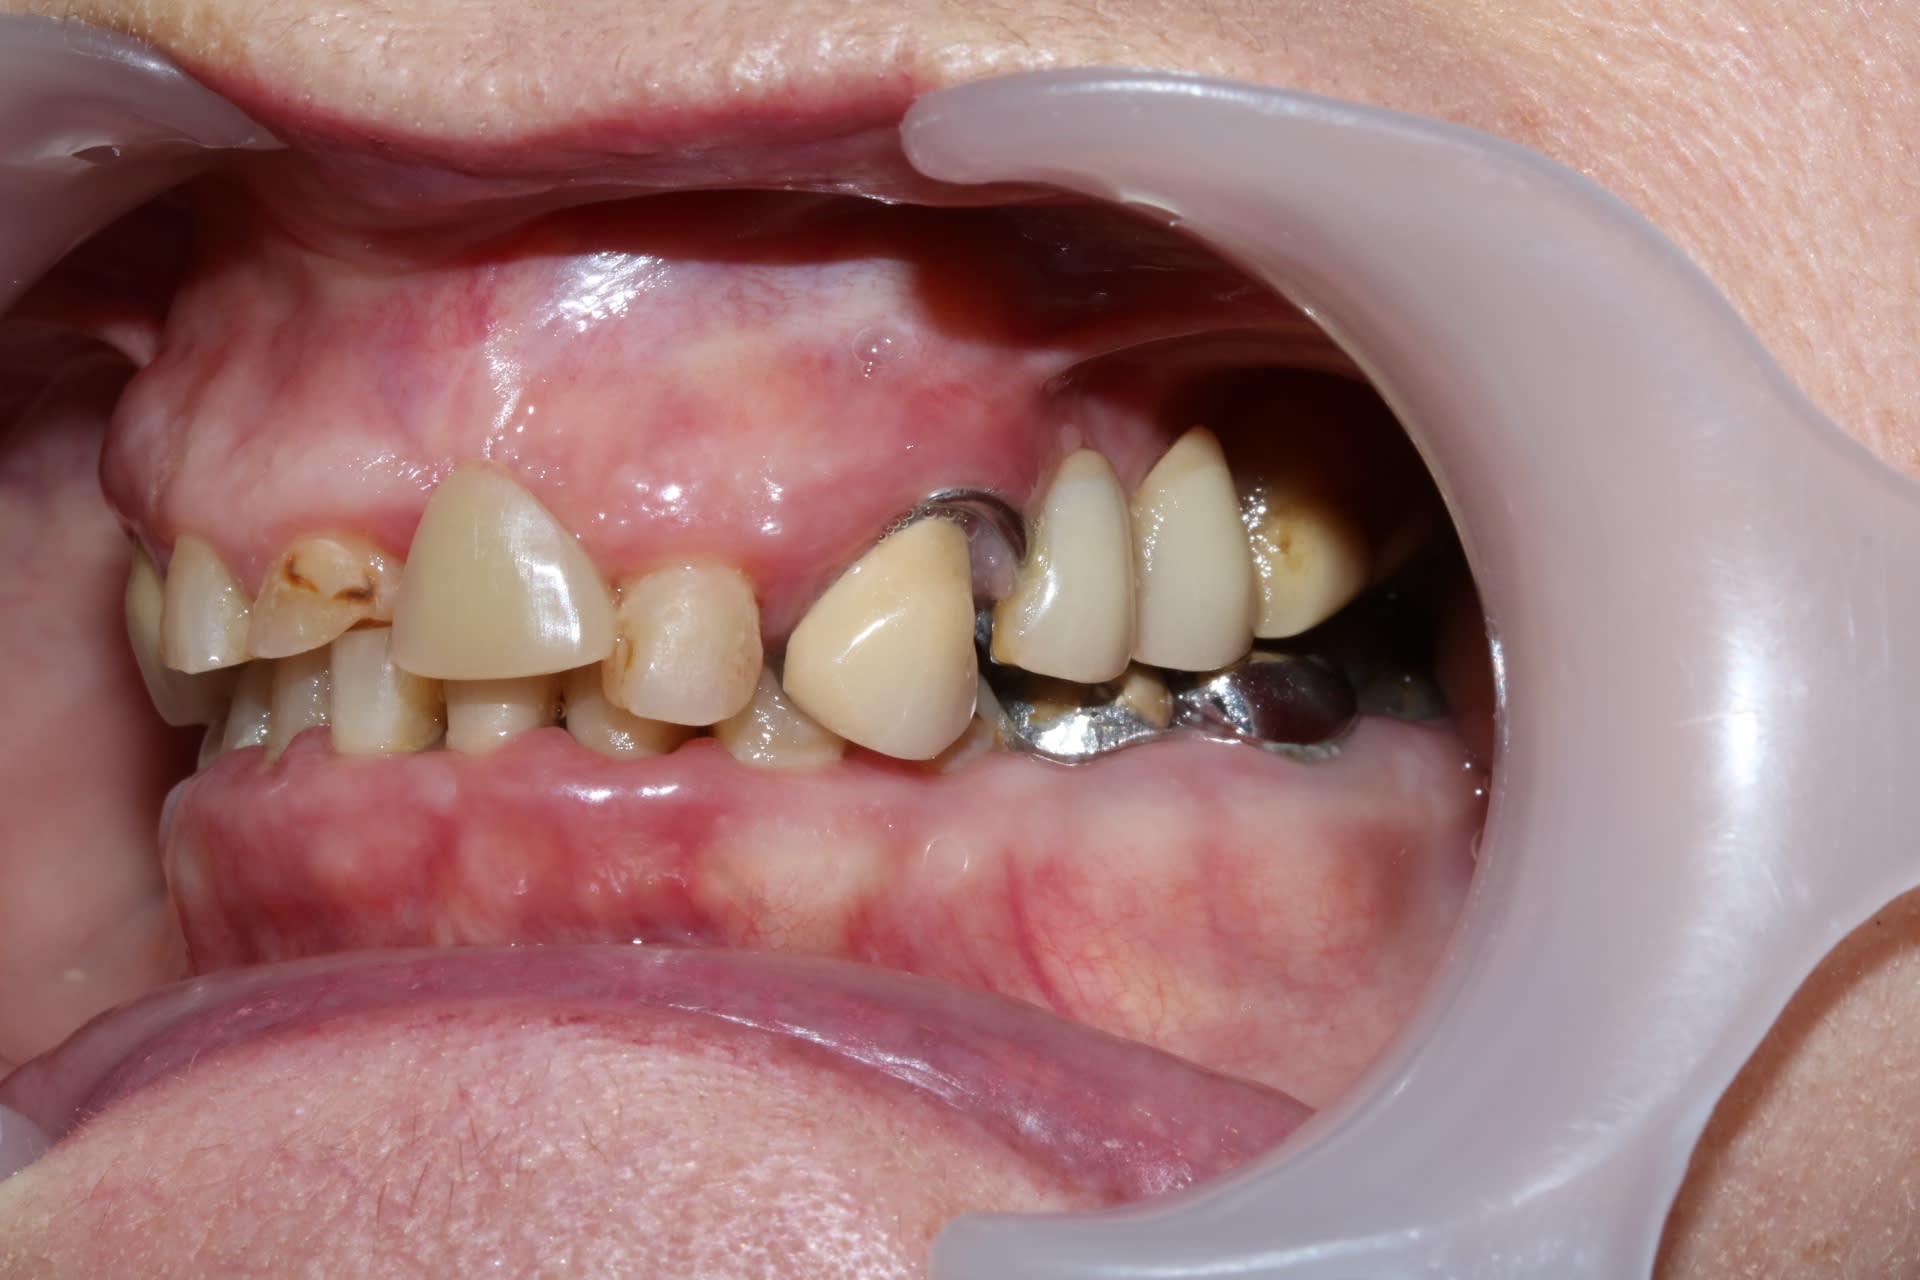

En bouche il y a un gros manque de DV, avec l’impression que tout a été reconstruit trop petit, trop bas, je ne comprend pas trop comment a été reconstruite la 23 qui semble beaucoup trop longue. Le stelite présente une particularité une selle mobile au niveau de la molaire S 2 pour "préserver la 23".

Bon , si tu ne regardes que la photo du bas :

tu as l impression que c est pas trop mal , hein?

et pourtant quand tu emboîtes le haut , ça s emboîte bien , mais tu vois bien que c est tout tordu qu il y a un truc qui ne va pas .

C est donc que le bas ne va pas non plus .donc faut couronner TOUTES les dents .

Pour le bas : à part de 33 à 43 tous le reste est sculpté de main de dentiste et prothésiste à la truelle. Donc .... j'ai pas confiance.